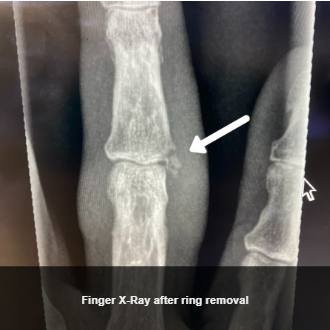

Upon arrival at the second hospital, the patient was assessed and an X-ray was done to further assess the patient’s finger injury before proceeding. There was a minor avulsion fracture noted, but no unstable injury, and the physician discussed with the patient their preferences around different ring removal approaches. The patient was very motivated to try to remove their ring intact, without ring cutting, if at all possible. Based on this, the physician then determined it was reasonable to attempt the Compression Device technique in this unique scenario. Because the physician knew that manipulation of the ring would need to be used for this technique, the physician reapplied a Ring Block.

After finger size was reduced, the physician then used proper ring manipulation techniques and lubrication, and was able to slowly manipulate the ring off of the finger, resulting in the ring being removed intact. A second X-Ray was performed after ring removal, and you can see above that there was no adverse change in the fracture, and the finger did not sustain any bruising or additional swelling and injury, and in fact as you can see in the photo below the finger had significant overall improvement.